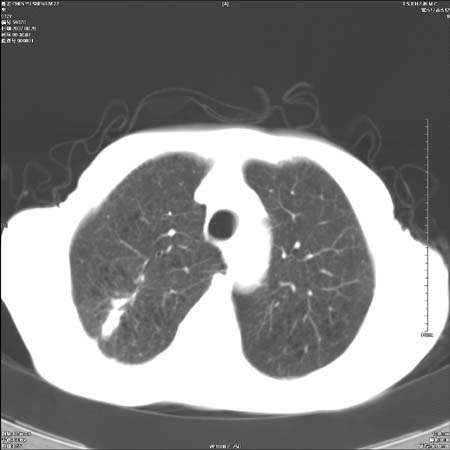

男性,72岁,既往肺结核,今复查。无前片对比。

纵隔窗

右侧中央型肺癌伴中叶不张可能性大,建议增强扫描.右上肺陈旧性肺结核.慢性支气管炎伴肺气肿.右侧少量胸腔积液.

右侧中央型肺癌伴中叶不张可能性大,建议纤支镜检查.右上肺陈旧性肺结核.肺气肿。

典型右肺中心型肺癌

右侧中央型肺癌伴肺不张可能性大,建议增强扫描.右上肺陈旧性肺结核.慢性支气管炎伴肺气肿.右侧少量胸腔积液.

右肺中心型肺癌

右侧中央型肺癌.上肺陈旧性肺结核.

1右侧中央型肺癌伴中叶不张2右侧少量胸腔积液3右上肺陈旧性肺结核

1.右肺中心性肺癌并右肺中叶综合征2。右侧胸腔少量积液3。右肺上叶结核球已钙化,4。慢支伴肺气肿

右侧中央型肺癌伴中叶不张可能性大,建议纤支镜检查.右上肺陈旧性肺结核.肺气肿。

右侧中央型肺癌伴中叶不张可能性大,建议增强扫描.右上肺陈旧性肺结核.慢性支气管炎伴肺气肿.右侧少量胸腔积液.

右侧中央型肺癌伴中叶不张

右肺中央型肺癌伴右肺中叶不张。

右上肺陈旧性肺结核。

支持右肺中心型肺癌并中叶不张,右上肺陈旧性肺结核钙化,右侧少量胸腔积液。

支持右侧中央型肺癌伴中叶不张可能性大,建议增强扫描.右上肺陈旧性肺结核.慢性支气管炎伴肺气肿.右侧少量胸腔积液.

支持 1右侧中心型肺癌伴中叶不张2右侧少量胸腔积液3右上肺陈旧性肺结核4双肺局限性肺气肿

1,右侧中央型肺癌.

2,右上肺陈旧性肺结核.

1.右侧中央型肺癌伴中叶不张,建议纤支镜检查.

2.右上肺陈旧性肺结核.

3.肺气肿。

4.右侧少量胸腔积液.

右侧中央型肺癌伴中叶不张并纵隔淋巴结增大,建议增强扫描.右上肺陈旧性肺结核.慢性支气管炎伴肺气肿.右侧少量胸腔积液。

右肺中心型肺癌并肺不张,陈旧性肺tb.慢支,肺气肿.

陈旧性肺结核.慢性支气管炎伴肺气肿,中央型肺癌伴中叶不张。

右侧中央型肺癌伴中叶不张可能性大;右上肺陈旧性肺结核.慢性支气管炎伴肺气肿

陈旧性结核是存在,但真正致命的却是右侧中心型肺癌。